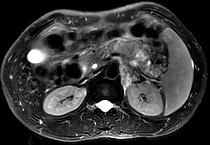

问题 男45岁、腹部胀痛不适、胃纳减退、体重减轻、中腹部可触肿块,影像检查如图,应诊断为 ( )

选项 A.急性胰腺炎 B.慢性胰腺炎 C.胰腺体尾部癌 D.胰岛细胞瘤 E.腹膜后淋巴结结核

答案 C